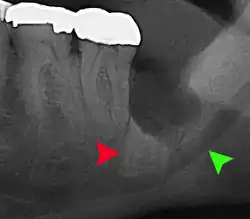

Las complicaciones a largo plazo pueden incluir complicaciones periodontales como la pérdida de hueso en el segundo molar tras la extracción de las muelas del juicio. La pérdida ósea como complicación tras la extracción de las muelas del juicio es poco frecuente en los jóvenes, pero está presente en el 43% de las personas de 25 años o más.[23] La lesión del nervio alveolar inferior que provoca entumecimiento o entumecimiento parcial del labio inferior y la barbilla ha registrado tasas que varían ampliamente del 0,04% al 5%.[23] El estudio más amplio es el de una encuesta de 535 cirujanos orales y maxilofaciales de California, en el que se registró una tasa de 1:2.500.[26]

La coronectomía es un procedimiento en el que se extrae la corona de la muela del juicio impactada, pero las raíces se dejan intencionadamente en su sitio. Está indicada cuando no hay enfermedad de la pulpa dental ni infección alrededor de la corona del diente, y existe un alto riesgo de lesión del nervio alveolar inferior.[32]

La coronectomía, aunque disminuye el riesgo inmediato para la función del nervio alveolar inferior, tiene sus propias tasas de complicaciones y puede dar lugar a repetidas cirugías. Entre el 2,3% y el 38,3% de las raíces se aflojan durante la intervención y deben extraerse, y hasta el 4,9% de los casos requieren una nueva intervención debido a la persistencia del dolor, la exposición de la raíz o la persistencia de la infección. También se ha informado de que las raíces migran en el 13,2% al 85,9% de los casos.[32]